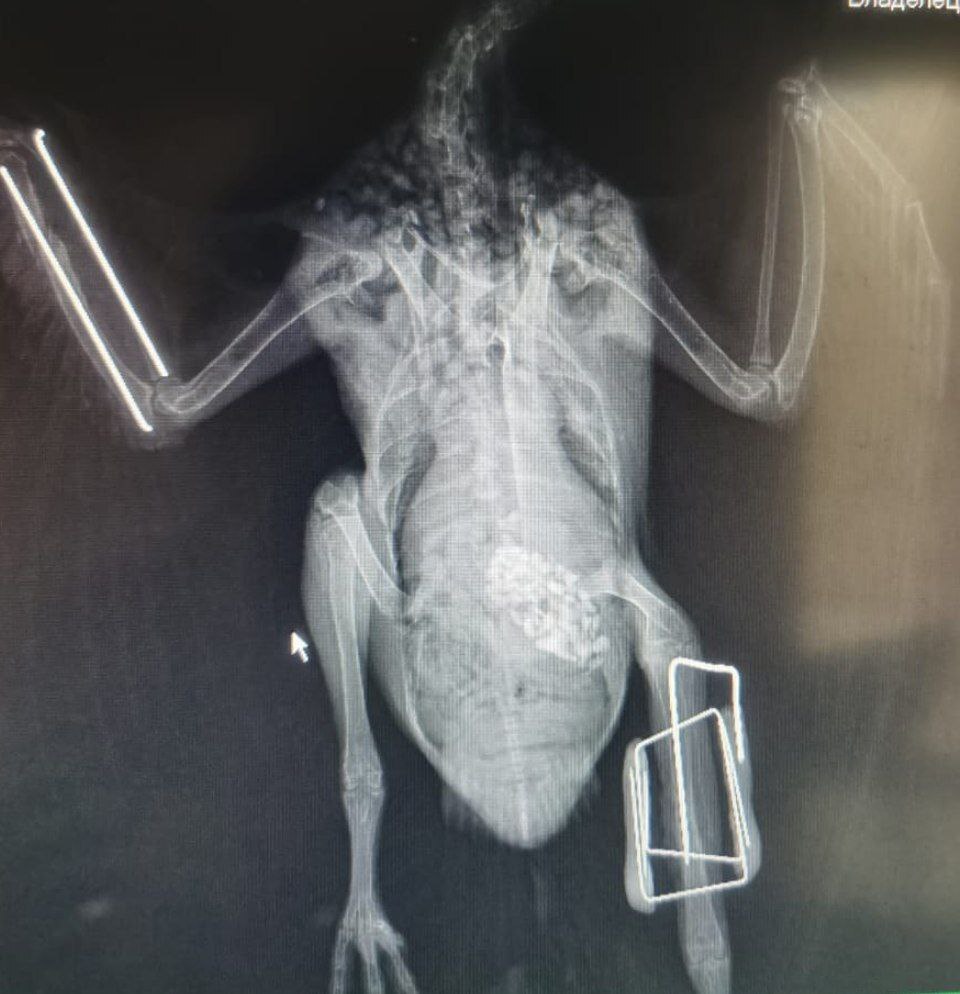

Сегодня расскажу немного про такой метод диагностики как рентген. В данном случае говорю только про своих, экзотических, пациентов.

Что это вообще такое - это метод лучевой диагностики, в котором используются рентгеновские лучи. При прохождении через ткани разной плотности они поглощают по-разному, поэтому мы и видим чёрно-белую картинку с 50 оттенками серого.

🩻 большой объём кишечника, который при повышенном газообразование может мешать визуализации органов на УЗИ

🩻 оцениваем легкие и сердечный силуэт параллельно с оценкой органов брюшной полости

🩻 хорошо видно костно-суставные патологии, это часто помогает найти причину хронической боли